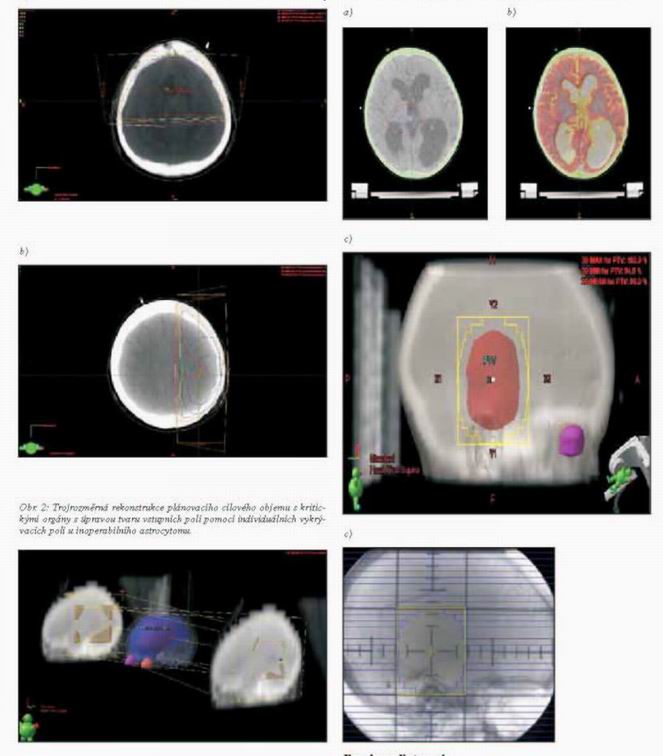

v kombinaci se stereotaktickou radioterapií. Nejčastějšími

technikami radioterapie mozkových nádorů jsou kombinace 2-4 polí,

jejichž tvar je upraven individuálními bloky nebo vícelamelovým

kolimátorem (obr. 1, 2). Plánování na RTG simulátoru, CT přístroji

(nejlépe za i.v. kontrastní aplikace) a vlastní ozařování se

provádí za fixace hlavy umělohmotnou maskou. Moderním způsobem

plánování cílového objemu je využití fúze CT/MR obrazů (obr. 3

a-d). Dávky záření a frakcionace jsou uvedeny v léčebné strategii u

jednotlivých diagnóz. Frakcionace 5x1,8 Gy/týden proti

5x2,0Gy/týden snižuje riziko pozdních ireverzibilních změn mozkové

tkáně zvl. u rozsáhlejších cílových objemů.

Obr. 1: Izodózní plán pooperačního ozáření lůžka tumoru

glioblastomu po totální exstirpaci brzdným svazkem lineárního

urychlovače 6 MV, a) technika dvou protilehlých laterolaterálních

polí, b) technika dvou protilehlých předozadních polí

Obr. 3: Určení plánovacího cílového objemu s využitím fúze obrazů u

pětiletého pacienta s inoperabilním pilocytickým astrocytomem: a)

pomocí CT vyšetření, b) fúze CT-MR obrazů, c) zobrazení z pohledu

svazku záření BEV, d) simulační snímek s obrysy lamel

vícelamelového kolimátoru o šířce lamel 5 mm v izocentru (Clinac,

Millenium 120 multileaf collimator).